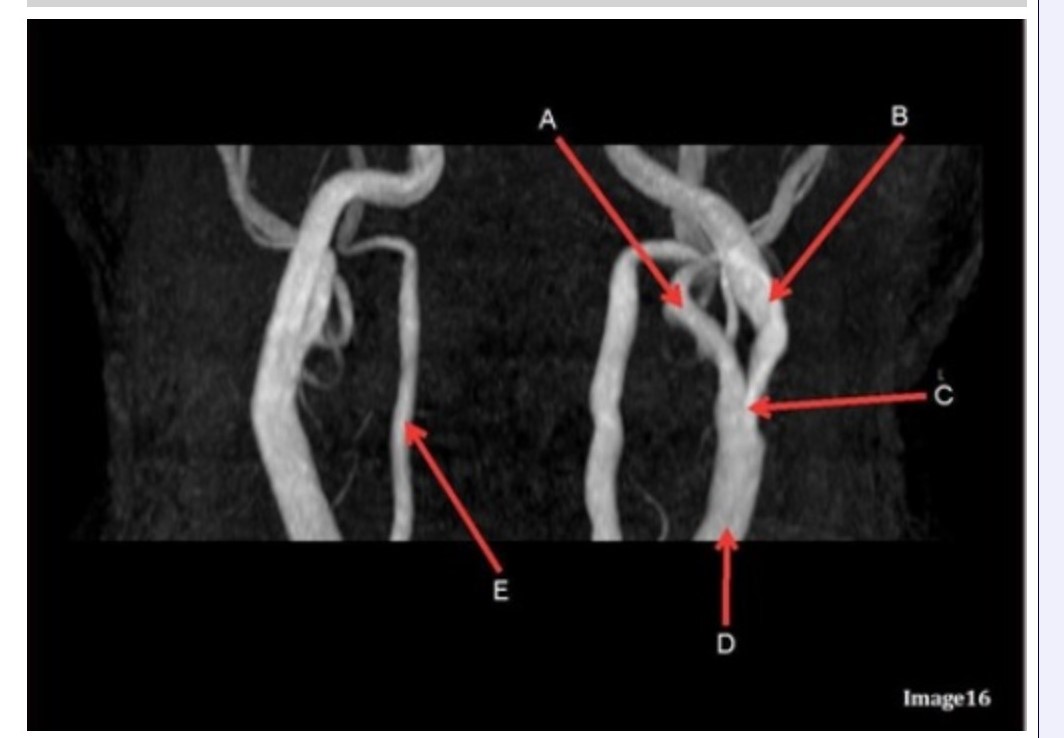

Letter B in Image 16 is pointing to:

A. Internal carotid artery

B. External carotid artery

C. Vertebral artery

D. Common carotid artery

E. Common carotid bifurcation

Letter E in Image 16 is responsible for blood supply to the:

A. Anterior brain

B. Posterior brain

C. Face

D. Upper extremities

Letter D in Image 16 is pointing to:

A. Internal carotid artery

B. External carotid artery

C. Vertebral artery

D. Common carotid artery

E. Common carotid bifurcation

Image 16 is an example of what type of MR image?

A. MR spectroscopy

B. MRA Circle of Willis

C. MRV intracranial circulation

D. MRA extracranial circulation

E. MRA intracranial circulation

Letter B in Image 16 is responsible for blood supply to the:

A. Anterior brain

B. Posterior brain

C. Face

D. Upper extremities

Letter E in Image 16 is pointing to:

A. Internal carotid artery

B. External carotid artery

C. Vertebral artery

D. Common carotid artery

Letter C in Image 16 is pointing to:

A. Internal carotid artery

B. External carotid artery

C. Vertebral artery

D. Common carotid artery

E. Common carotid bifurcation

Letter A in Image 16 is pointing to:

A. Internal carotid artery

B. External carotid artery

C. Vertebral artery

D. Common carotid artery

E. Common carotid bifurcation

Letter A in Image 16 is responsible for blood supply to the:

A. Anterior brain

B. Posterior brain

C. Face

D. Upper extremities